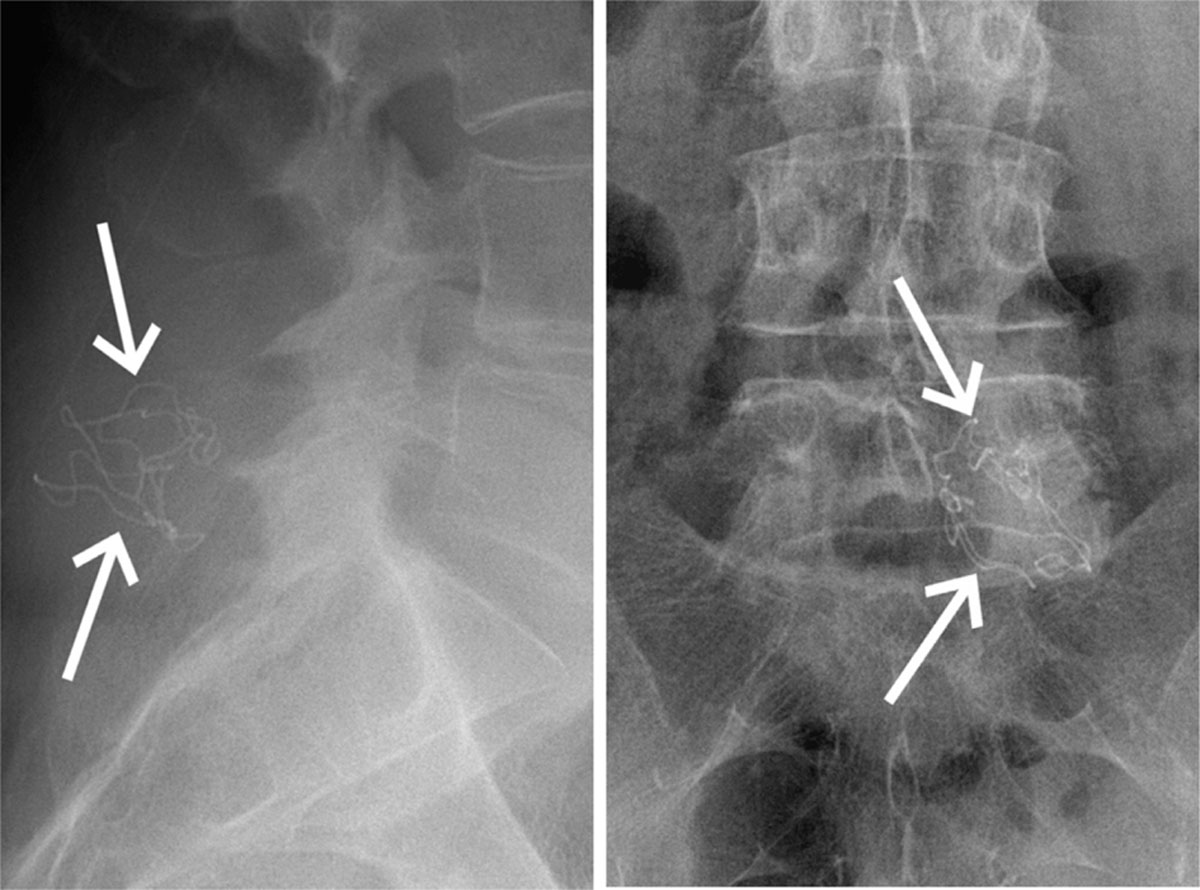

또한, 거즈 중앙에는 청색 선이 일자로 그어져 있으며, 이 선은 방사선에 반응하는 바륨 설페이트(Barium sulfate)를 함유하고 있어, 전술적 후송 이후 군치료시설(Military Treatment Facility, MTF)에서 엑스선 검사 시 거즈의 위치를 확인하는 데 도움을 준다.

| BaSO4 화학식 | 거즈 중간의 청색 스트립이 BaSO4다. | BaSO4는 방사선 반응을 하면 하얀 선으로 위치를 확인할 수 있다. |

* Barium sulfate, BaSO4는 바륨과 황산이온이 결합한 무기 화합물이다. BaSO4는 방사선 불투과성질을 지녀, X-Ray나 CT 검사에서 거즈를 명확히 식별할 수 있도록 한다. 또한 BaSO4는 물에 잘 녹지 않아 체내에 흡수되지 않으며 인체에 무해하여 방사선 조영제로도 사용된다.